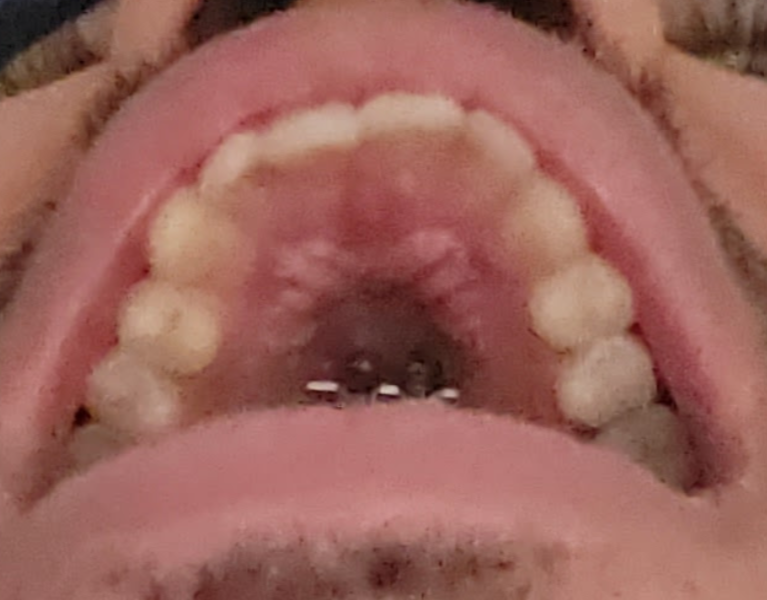

Before

After

I finished my expansion about 9 months ago, and I got my braces on 1 month ago. I did around 10 mm of expansion. I’m planning to get a bimax once my treatment is over

After

I finished my expansion about 9 months ago, and I got my braces on 1 month ago. I did around 10 mm of expansion. I’m planning to get a bimax once my treatment is over